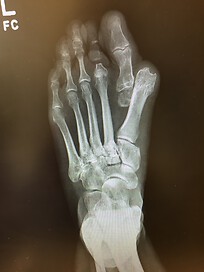

The x-rays were shocking! The bones in my left foot were literally a shock to me and the entire office staff. The bones had been separating significantly. I eventually was diagnosed with severe RA.

I knew there was something wrong with my left foot, but I was completely surprised by the diagnosis. I had two surgeries to put my foot back together and started on my RA journey of medications and complete change in lifestyle, including being determined completely disabled.